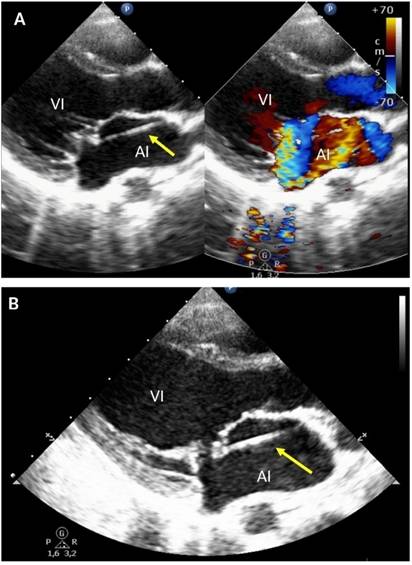

Presentamos el caso de una paciente de 10 años que acude a nuestro centro por cuadro clínico de un año de evolución, caracterizado por deterioro progresivo de la clase funcional, asociado a ortopnea y episodios sincopales recurrentes. En el examen físico se encontró el precordio hiperdinámico, con choque de la punta desplazado hacia abajo y a la izquierda, asociado a soplo holosistólico a nivel de ápex, irradiado hacia la axila. El ecocardiograma transtorácico evidenció regurgitación mitral severa con prolapso de la valva anterior, así como una banda lineal anormal al interior de la aurícula izquierda, uniendo la valva anterior de la válvula mitral con el techo de la aurícula izquierda (fig. 1). La experiencia quirúrgica en esta cardiopatía es extremadamente limitada y con frecuencia requiere de excisión de la cuerda tendinosa anómala, plastia de la valva anterior y anuloplastia mitral posterior. Este constituye el segundo caso reportado en la edad pediátrica1-4.

Figura 1 Ecocardiograma transtorácico. A) En proyección eje largo paraesternal izquierdo se muestra en 2 D y Doppler color la presencia de una banda lineal anormal al interior de la aurícula izquierda (flecha amarilla), así como el jet de regurgitación excéntrico de la insuficiencia severa de la válvula mitral. B) Acercamiento de la válvula mitral que demuestra el prolapso de la valva anterior secundaria a la tracción ejercida por la cuerda auricular izquierda accesoria. El color de esta figura solo puede apareciarse en la versión electrónica del artículo.